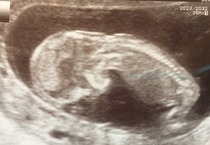

MrsZumbaDancer · 05/02/2016 13:17

Big long leg stretched out! Baby was pretty chilled for measurements then had a little dance around.